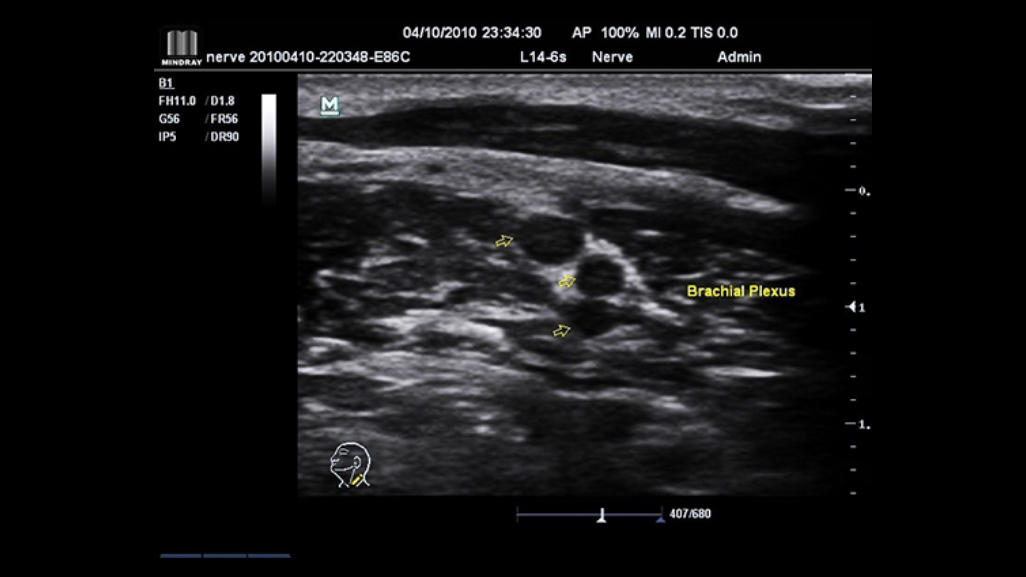

With its ergonomic mobile trolley same with performance and features comparable to that of conventional cart-based systems, the M7 Premium provides you mobility with power and improves your productivity. To sum it up, the M7 Premium delivers you the power and productivity of a full-sized system in a hand-carried size.

iScanHelper

Dedicated inbuilt tutorial software.

┬Ę Anatomical diagram illustrations including schematic and ultrasound picture

┬Ę Standard ultrasonogram comparison with real-time scanning

┬Ę Scanning reference picture demonstrating appropriate patient position and probe placement

┬Ę Tips on scanning skills and diagnostic information